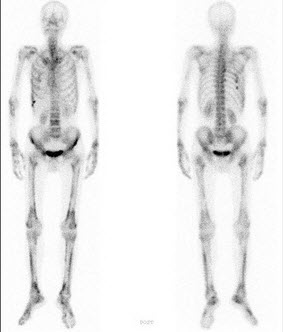

125、单项选择题

男,48岁,肺小细胞癌化疗中,诉全身疼痛,行全身骨显像如图,可能的诊断是()

A.广泛骨转移瘤

B.颅骨有冷区

C.大致正常的影像

D.颅骨有“甜面圈”征

E.是超级骨显像